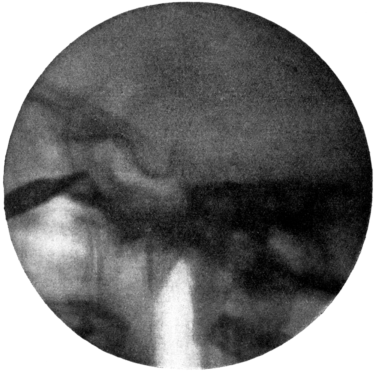

| 254. | Skiagram showing a Tumour of the Larynx | 476 |